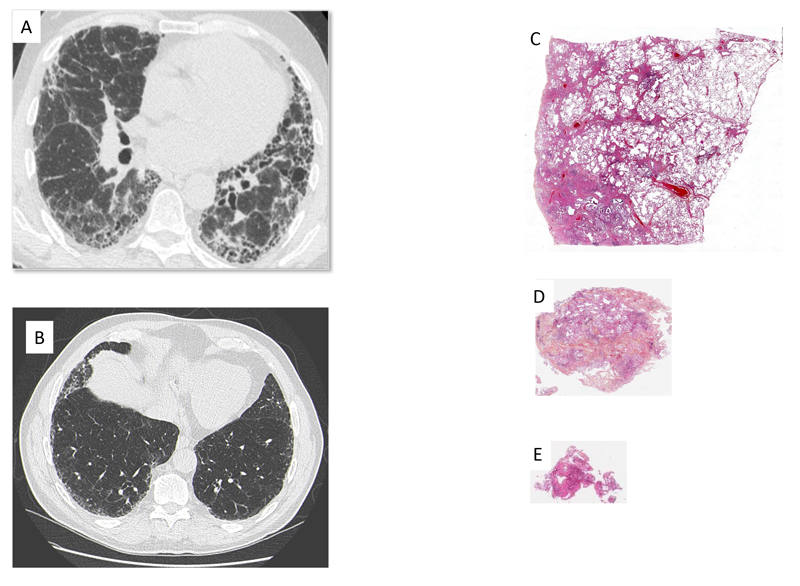

Figure 3 Scanner représentatif de (A) Pneumopathie interstitielle commune, (B) Pneumopathie interstitielle commune probable. Prélèvement histologique représentatif prélevé (A) par biopsie pulmonaire chirurgical, (B) par cryobiopsie, (C) par biopsie transbronchique.